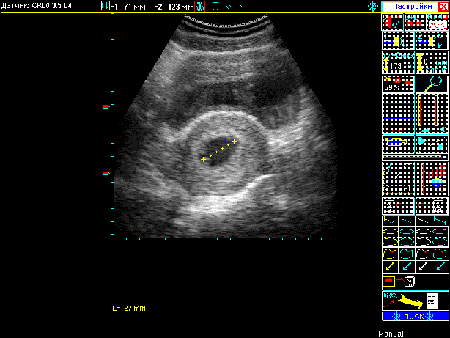

1. Измерение внутреннего диаметра плодного яйца

Измерение внутреннего  диаметра плодного яйца

2. Фиксация в протоколе результатов измерения

Фиксация в протоколе  результатов измерения

3. Наблюдение результата расчета

Наблюдение результата  расчета

Схема 2. Последовательность получения результатов расчета срока беременности.